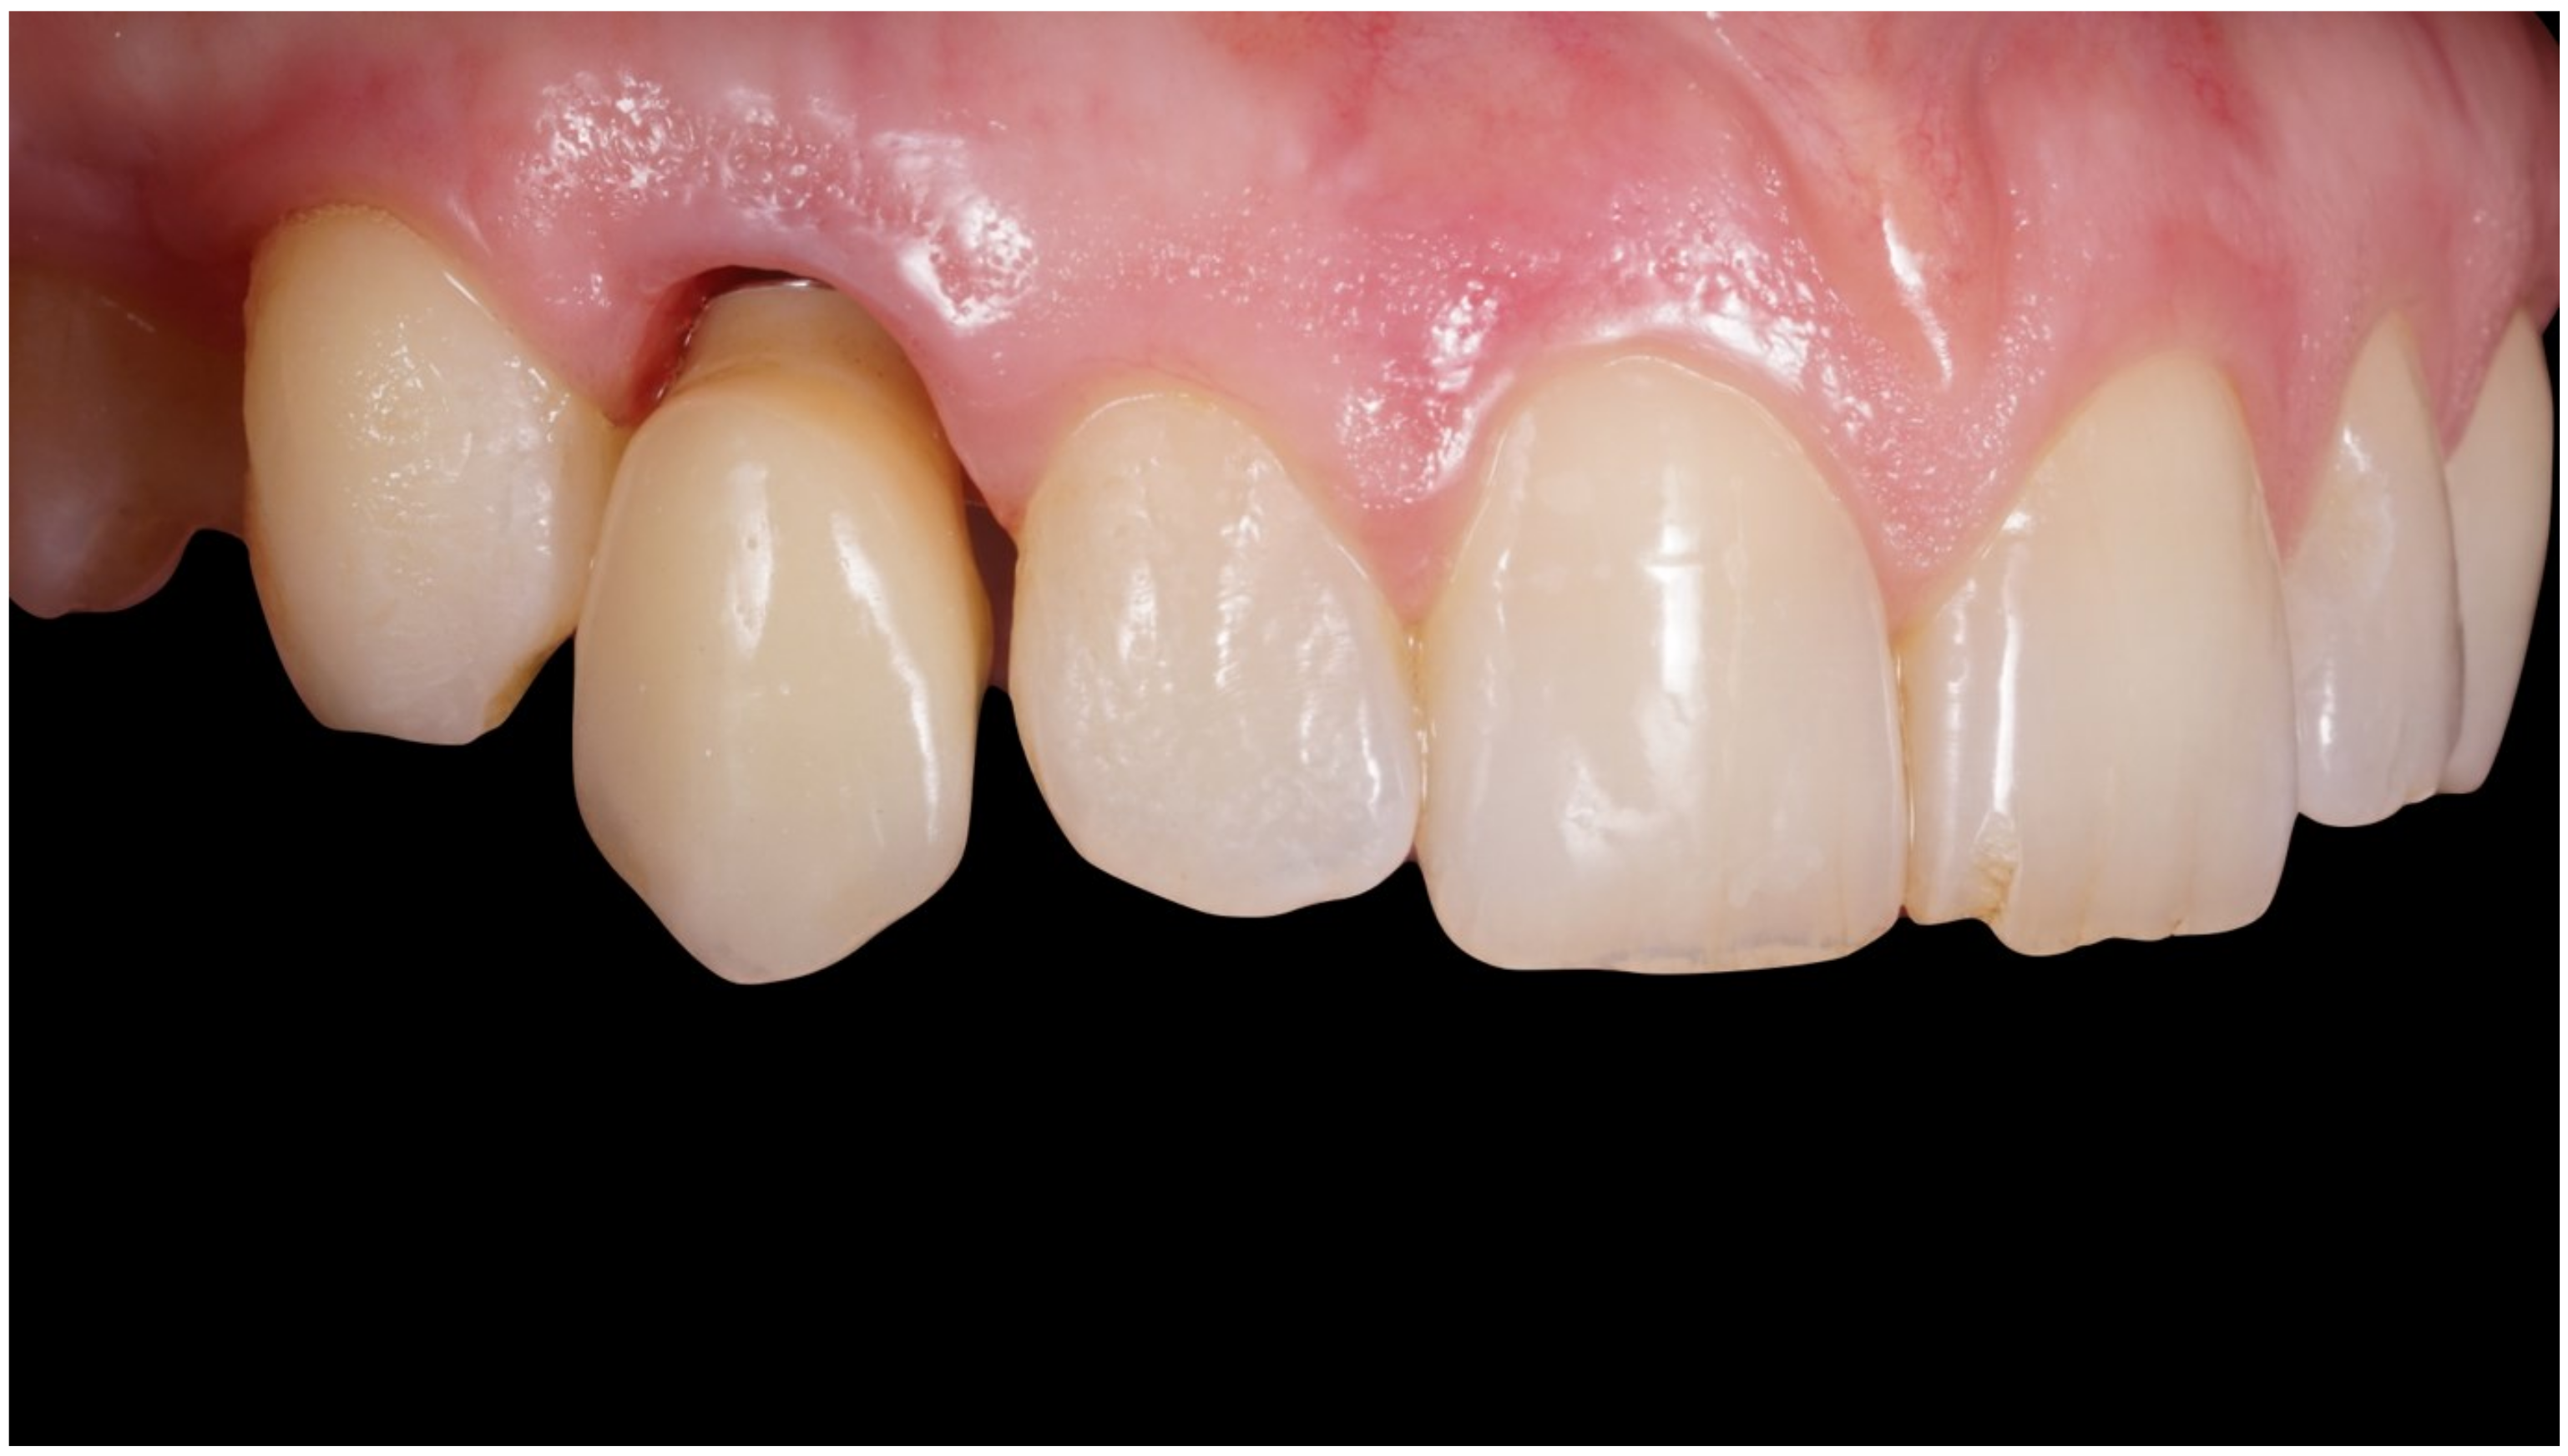

Figure 6.

Healing of soft tissues around the temporary crown.

Figure 7.

Scan abutment in position to record intraoral scan.